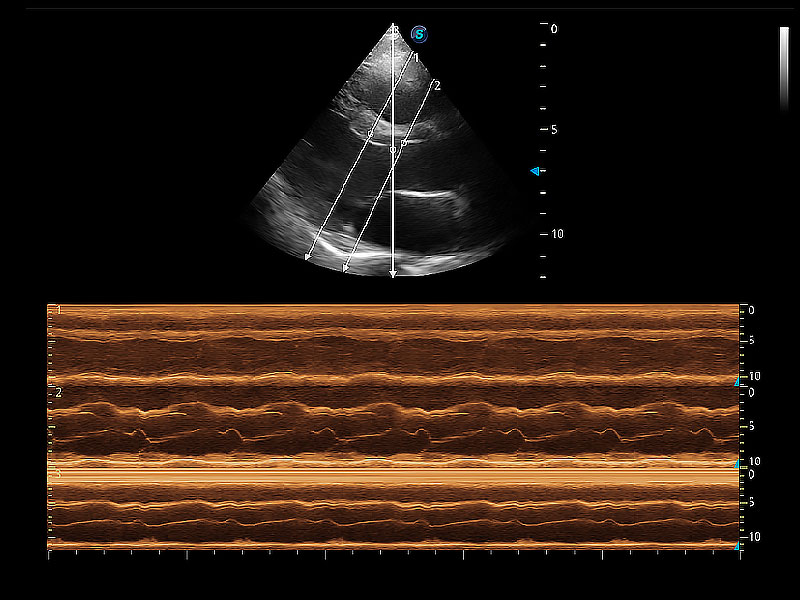

通过360度任意调节3条M型取样线,在同一心动周期上观察心脏不同位置的运动曲线,得到准确的心功能测量数据,有效评估心肌运动及左心室功能。

ProPet 80 配备了丰富的心脏探头群、先进的成像技术和专业的心脏测量工具,可帮助动物医生为不同体型和生理结构的动物提供心脏和心肌功能的全面评估。